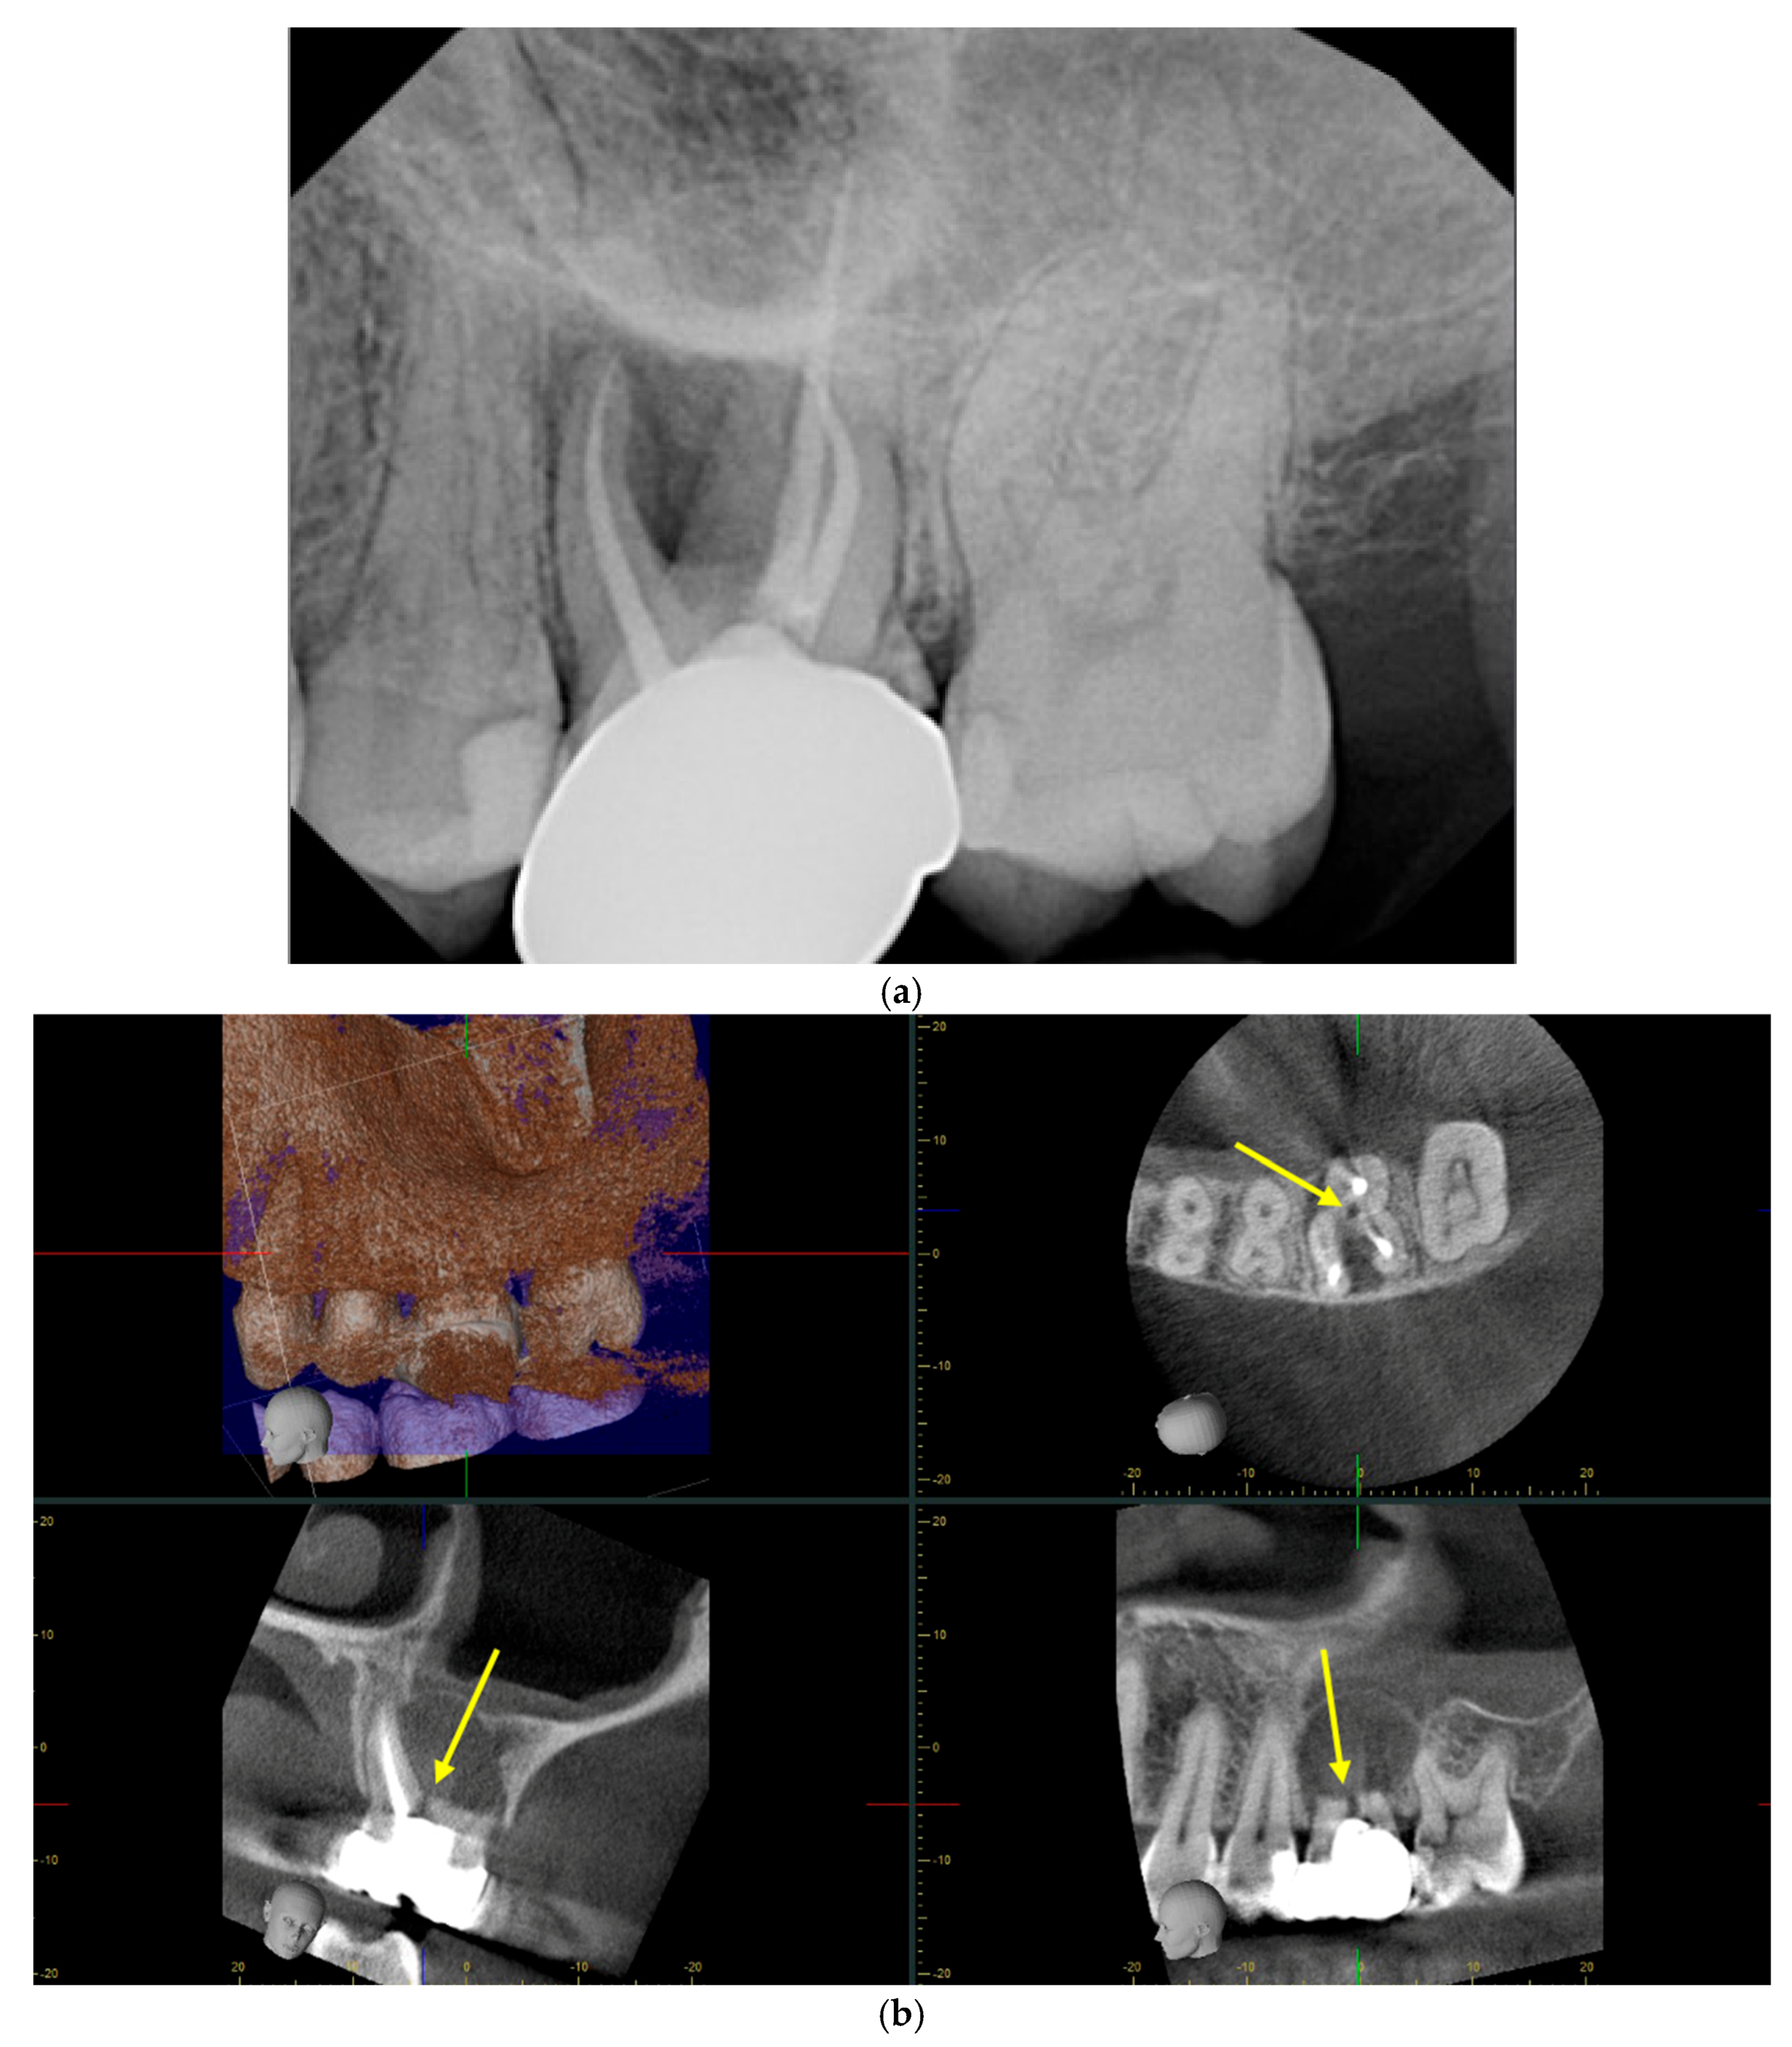

Radiographs play a critical role in the diagnosis of endodontic perforations, providing crucial imaging that guides clinical decision-making throughout the treatment process. Endodontic perforations are often clinically asymptomatic, making radiographical methods vital for accurate diagnosis [19]. Traditionally, periapical radiographs have been used as the primary imaging technique in the diagnosis, treatment, and post-operative follow-up of endodontic perforation [2,19]. However, periapical radiographs have limitations due to their two-dimensionality, making the determination of the location and severity of perforations challenging [2,3,19]. Additionally, it is sometimes impractical to use two-dimensional imaging, as perforations are often superimposed on intact root structure and filling materials, which creates artifacts, making them difficult to distinguish [2]. In recent times, cone-beam computed tomography (CBCT) imaging systems have become more popular in the diagnosis and treatment of endodontic perforations [2,19]. CBCT imaging allows providers to see in three dimensions, ultimately providing more conclusive information through fine detailing of root canal anatomy and any present lesions [6,19,20]. In general, imaging with a small FOV is preferred for the detection and treatment planning of perforations due to an increased image quality caused by the reduction in scatter [2]. In recent years, clinicians have debated whether CBCT imaging is a superior radiological diagnostic method or if traditional periapical radiographs should continue to be the primary radiographic diagnostic method.

4.7. CBCT versus Periapical Radiographs

Figure 2. Periapical radiograph versus CBCT illustrating the same furcal perforation on tooth #14: (a) in the periapical radiograph, the perforation is not well visualized due to the angulation of the image; (b) in this series of CBCT images, the perforation is much easier visualized (yellow arrows), attributed to the multiple planes of view.